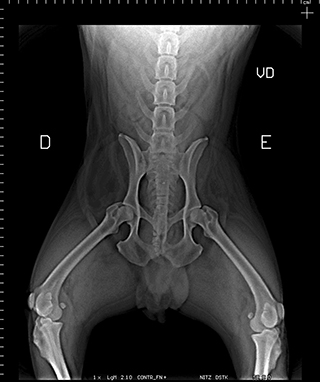

Radiologia Digital Direta / Digital Radiography

As radiografias geradas digitalmente podem ser transmitidas para iPad Apple®, notebooks e smartphones.

iPad com tela Retina Apple® possibilita a visualização das imagens com maior qualidade diagnóstica.

O treinamento aborda a geração das radiografias, a edição digital das imagens, e também a

escolha adequada de técnicas radiográficas como kilovoltagem, corrente elétrica e tempo de exposição.